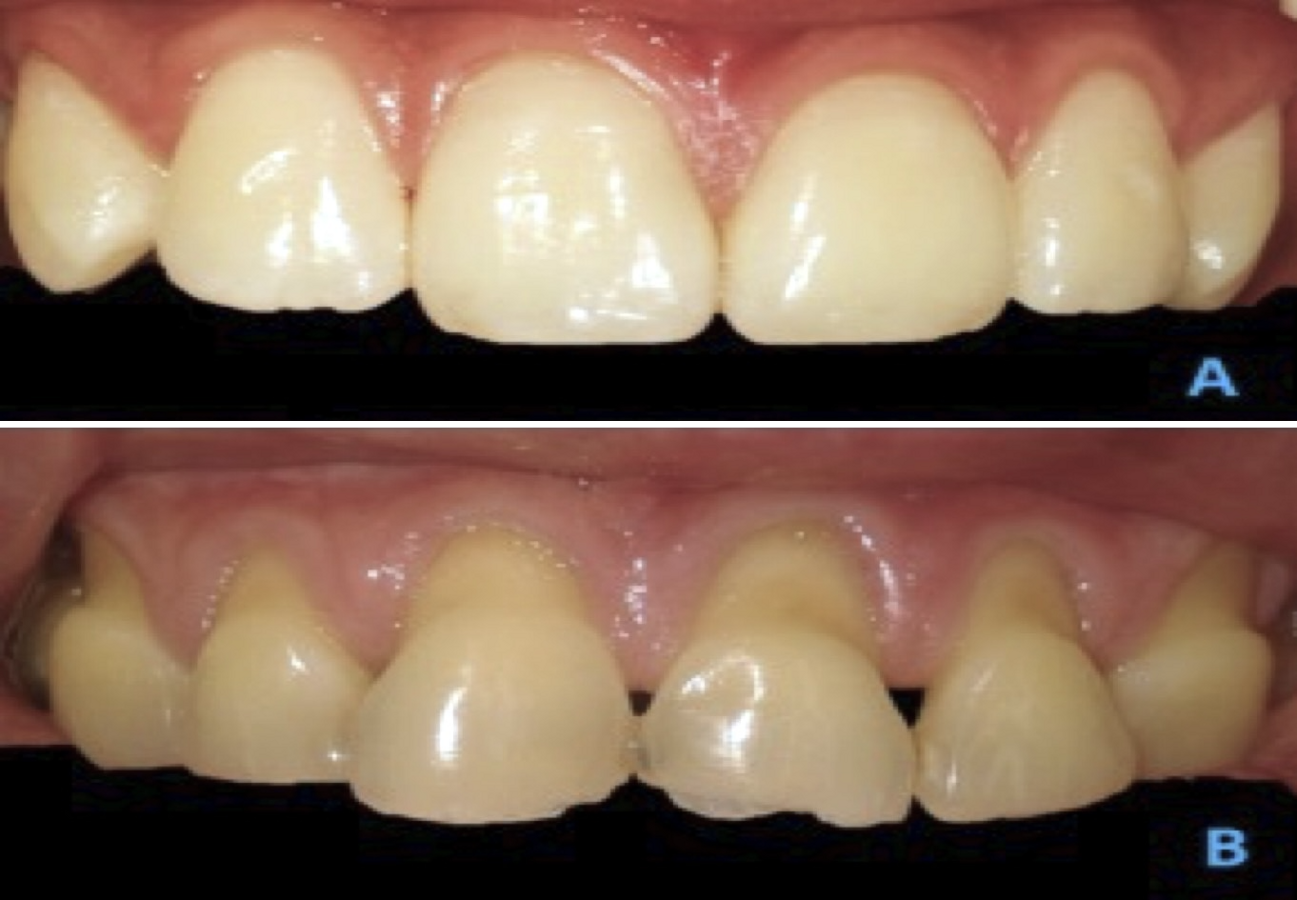

Figura 1. Paciente 12 años con anatomía gingival y estructura dentaria prístina, y línea roja sin alteraciones. Fotos: Imaáenes de los autores

Figura 2. A) Paciente 14 años con cinturón cervical. B) Paciente de 18 años, con cinturón cervical e influencia de desmineralización.